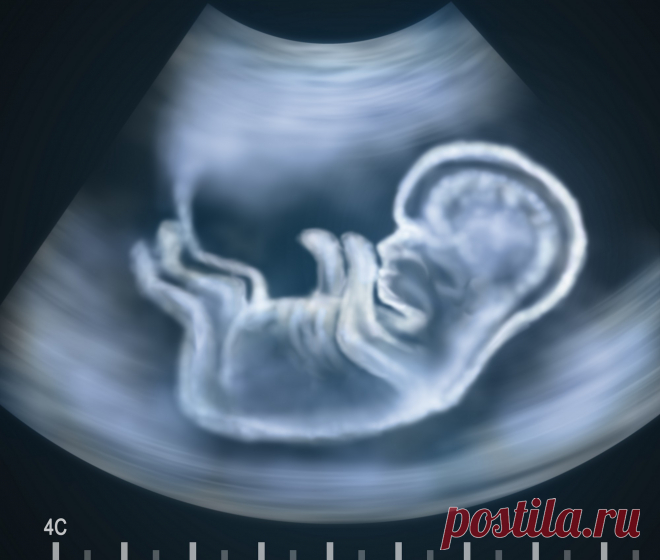

Пренатальная диагностика заячьей губы и волчьей пасти